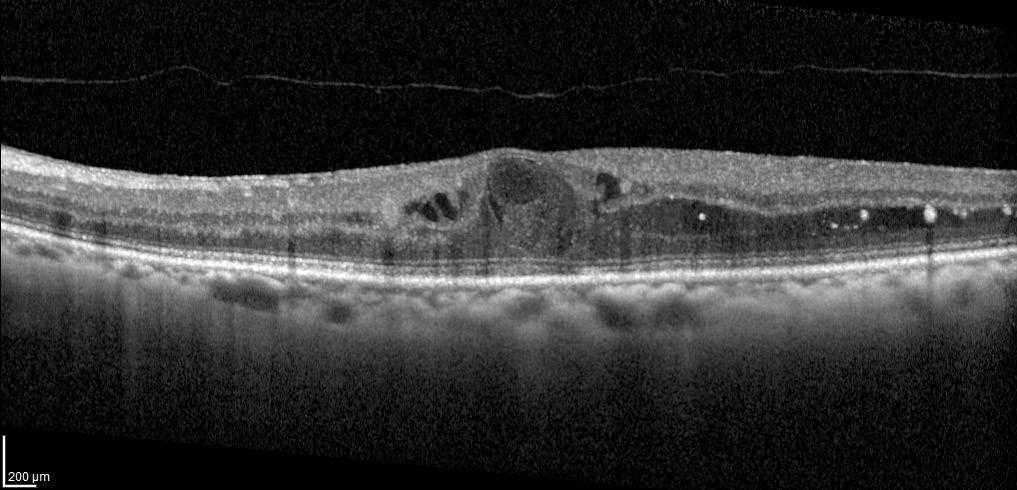

Results of a phase 2a study investigating RZ402 treatment for diabetic macular oedema (DME) show that the novel, orally administered plasma kallikrein inhibitor (PKI) had a favourable safety profile and potential efficacy based on measured change in central subfield thickness (CST), reported Arshad M Khanani MD.

“RZ402 is the first PKI and first oral therapy of any class to demonstrate CST improvement in eyes with DME. The phase 2a study results support advancement of RZ402 into longer duration phase 2b/3 studies.”

Interest in targeting the kallikrein-kinin system (KKS) stems from the knowledge diabetes causes injury to retinal blood vessels—which leads to vascular permeability, inflammation, and coagulation—and understanding the KKS is the first line of defence against vascular injury. Preclinical and clinical data also implicates the KKS as a VEGF-independent cause of DME.

The phase 2a study of RZ402 randomised 94 patients to treatment with placebo or RZ402 50 mg, 200 mg, or 400 mg. Patients took their assigned treatment once daily for three months and were then followed for an additional month once off treatment.

Eligible patients had ETDRS BCVA ≤78 letters and met CST thresholds (males, >320 microns; females, >305 microns).

Mean CST at baseline was 408 microns in the placebo group and about 30 to 50 microns higher in the RZ402 groups. Otherwise, mean baseline characteristics were well-balanced across the study groups.

Safety was a primary endpoint, and the collected data showed that adverse events were generally mild and occurred at a similar incidence in the placebo and RZ402 groups. No serious adverse events were judged as related to the study drug, no adverse events associated with other PKIs, and no remarkable changes in electrocardiography, vital signs, or safety laboratory tests.

Change in CST was also analysed as a primary endpoint and showed clinically significant reductions in the RZ402 groups compared to controls. After three months, CST increased by a mean of 3 microns in the placebo group and decreased by a mean of 21 to 47 microns in the RZ402 groups, although not in a dose-response fashion. More RZ402 benefit was seen in the subgroup analysis of patients with baseline CST ≥400 microns without a dose-response effect.

“The lack of a dose response likely can be explained by drug saturation of PKI activity past the 200 mg dose,” Dr Khanani said. BCVA was investigated as a secondary endpoint, but did not show a benefit of RZ402.

“We know that BCVA does not always correlate with CST and fluctuates in patients with DME. In fact, there was an early anomalous increase in the placebo group,” Dr Khanani said.

“However, there was a trend for some improvement over time in the RZ402 groups, and we hope that we will see it has a functional benefit in a longer study.”